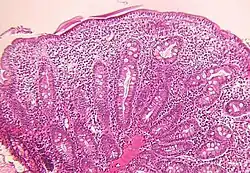

Small bowel

Microscopic examination of a biopsy of the small bowel in these patients shows villous atrophy with low or no mononuclear cell infiltration of the lamina propria nor specific abnormalities involving the epithelium. The amount of villous atrophy does not explain the severity of the diarrhea.